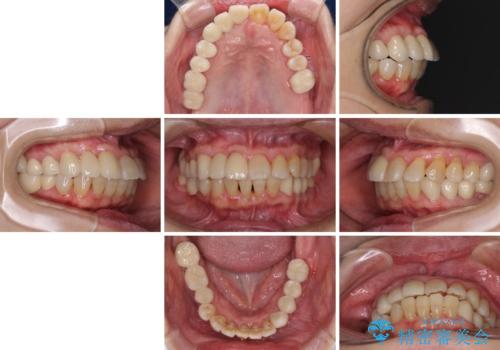

数多くの外科処置を行ったため、治療期間は長期間となりました。

一方、外科処置をしっかりと行ったことで、歯周病の状態は改善され、安定した状態にしあげることができました。